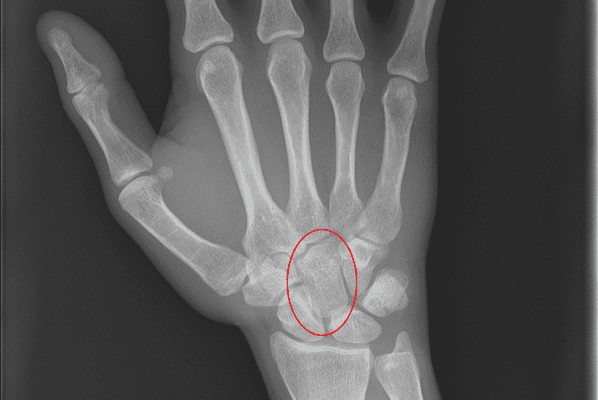

Carpal bone Fractures can be difficult to detect on conventional Xray and may require CT for diagnosis.

Where Carpal Fracture is suspected, X-rays in the anteroposterior (AP), lateral and oblique views are needed. Bone scans and CT scans are sometimes helpful if the fracture is not obvious on plain X-ray and should be considered where fracture is still suspected.

The most common Carpal dislocations are the lunate, the lunate with a scaphoid fracture, and perilunate dislocation.Carpal dislocations can lead to chronic pain and wrist instability. They are difficult to diagnose and are often missed.